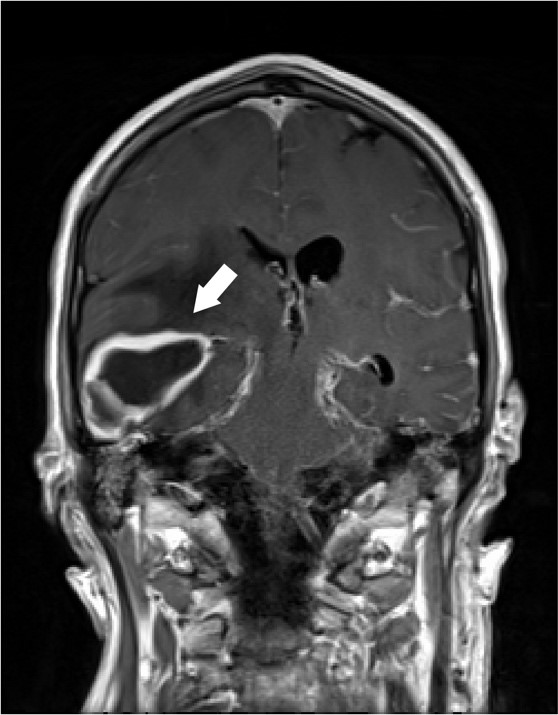

Figure 1. Coronal T1 post-contrast MRI demonstrating the ring-enhancing mass in the right temporal lobe (arrow).

A 62 year old male with unknown past medical history was dropped off at the emergency department by EMS after being found altered with concern for IV drug use. On presentation he was febrile to 104.5o F, tachycardic, and although he was initially responsive, his mental status deteriorated. Labs were drawn and broad-spectrum antibiotic coverage with vancomycin, cefepime, and metronidazole was initiated in the ED. He then had a tonic-clonic seizure event and was given intravenous levetiracetam. A CT brain showed a right inferior temporal lobe lesion, initially interpreted as likely glioblastoma multiforme, causing subfalcine and uncal herniation. MRI revealed a ring-enhancing mass measuring 3 cm x 3 cm x 3 cm in the right temporal lobe with significant surrounding edema. CT of the temporal bones also revealed right mastoiditis (Figures 1 and 2).